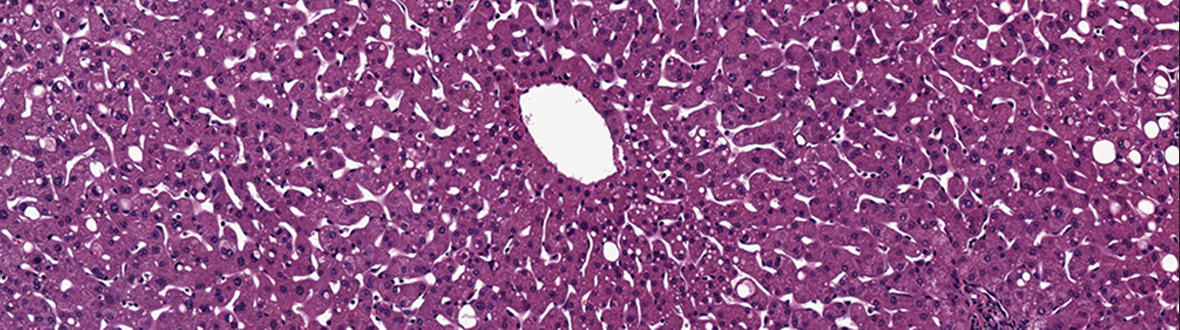

LifeNet Health’s LifeSciences Division created a human tissue and cell-based in vitro biology platform by leveraging its innovative technology-driven transplantation and preclinical research programs. The LifeSciences Division developed a vertically integrated supply chain for human tissue recovery and cell preparation, which supports the increasing demands for human biospecimens, primary cells and hepatocytes for scientific research, drug discovery and safety testing. The application of three dimensional matrices and human cellular models will enable significant scientific improvements for more relevant biologic experiments.

LifeSciences products and services include: human biospecimens, hepatocytes and other primary cells, cell culture media including human ECMs (HuGentra), oncology 3D HuBiogel™- based biology testing services, and custom requests.